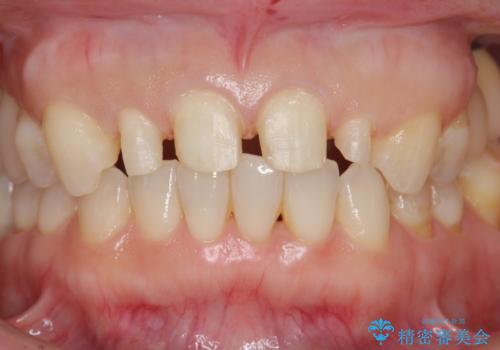

前歯が大きいのが気になる セラミックで整えたい

- 前歯が大きいのを揃えたいとのことでした。

少し削って長さを短くして様子を見ましたが、どうしても気になるとのことでした。

隣の前歯が小さいため、4本被せてバランスをとりました。